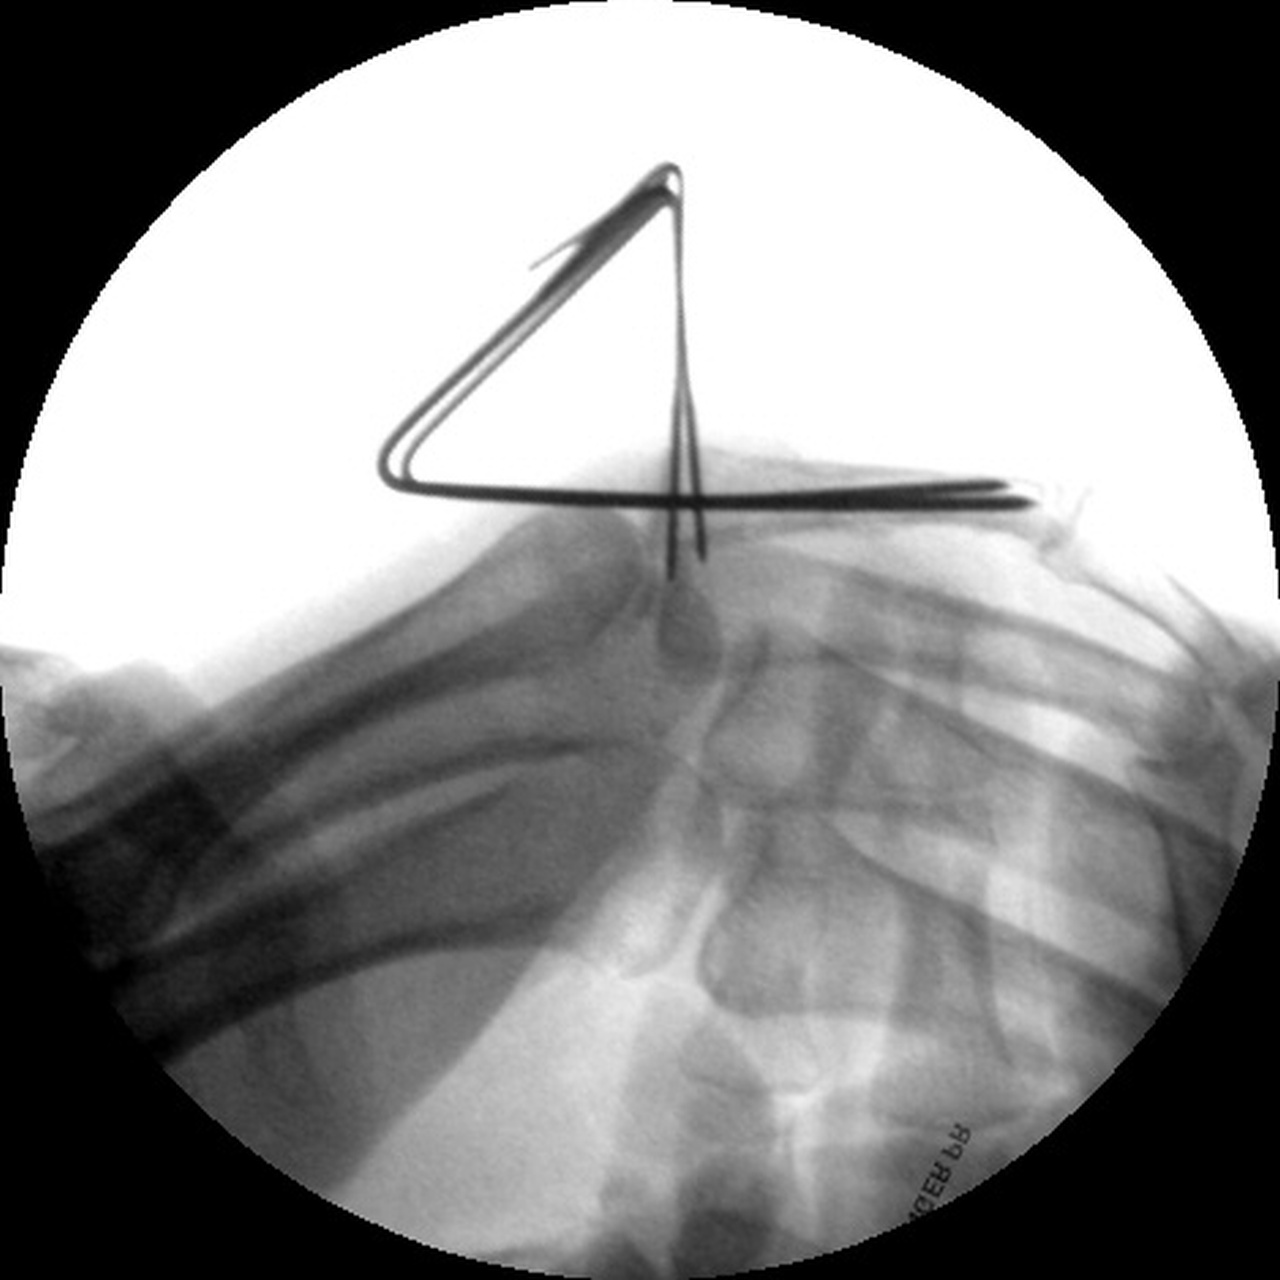

| Percutaneous pins placed across the fracture line and also dorsal to palmar into the proximal fracture fragment. |

| The pins were left protruding through the skin, and were bent toward each other to form a common zone of overlap which was glued together with aquaplast to form an external fixation construct. |